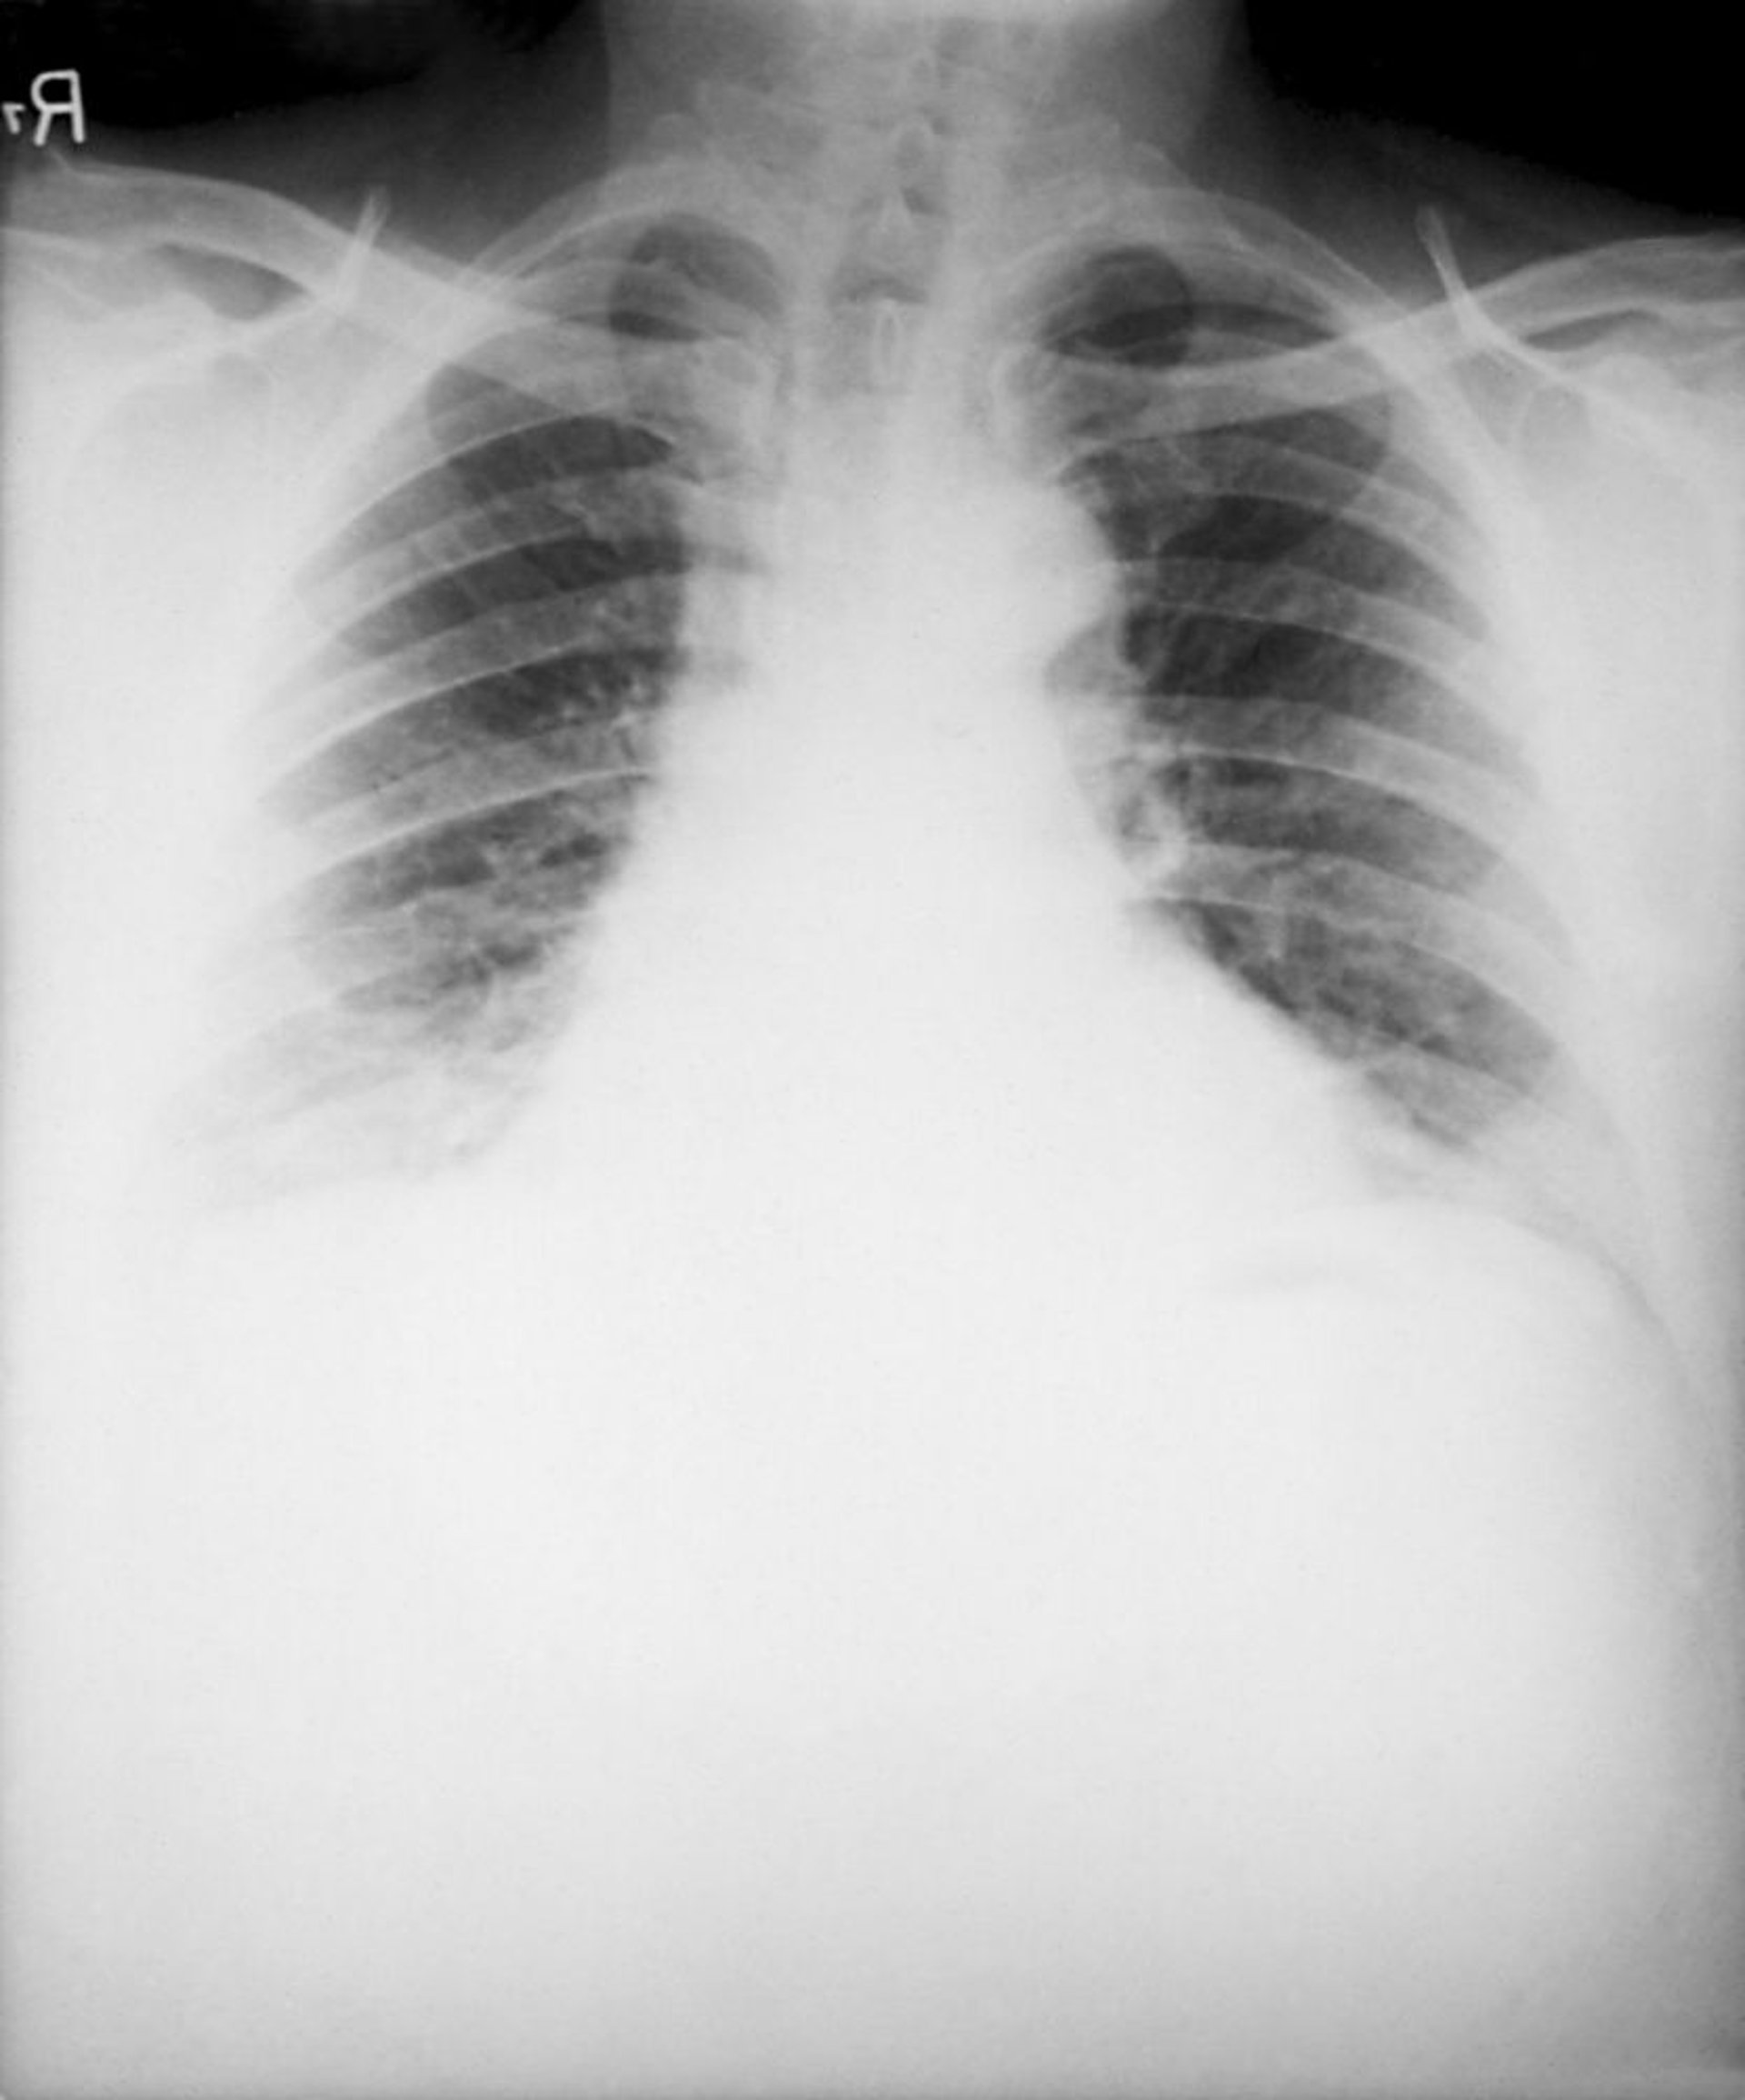

Carbonchio (antrace) (inalatorio)

I reperti tipici della forma inalatoria del carbonchio (antrace) alla radiografia del torace includono uno slargamento del mediastino causato da linfoadenite mediastinica necrotizzante emorragica e versamenti pleurici bilaterali. Gli infiltrati polmonari sono rari.

Image courtesy of the Public Health Image Library of the Centers for Disease Control and Prevention.